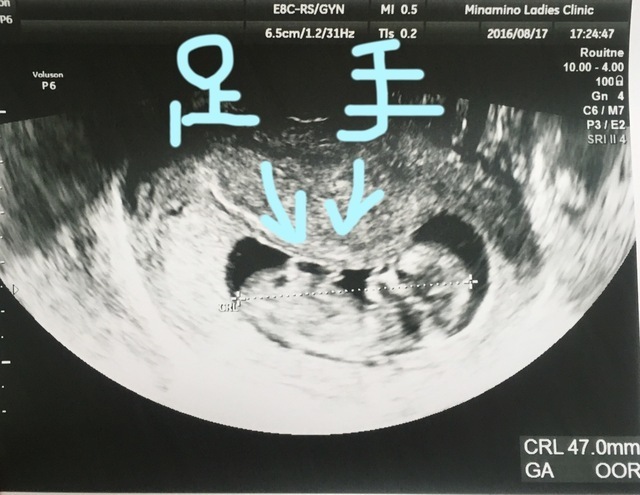

9週0日(9w0d・女の子)|nekonie さん(26歳)

少し見にくいかもしれませんが、よく見ると手をXの形にしているように見えます。

こんなに小さい時から、こんなポーズをしているのはなかなか見れないんじゃないかと思い、家族や友達に見せたらみんなびっくりしていました。キューピーちゃんみたいでとてもかわいくて、一番思い入れのあるエコー写真です。